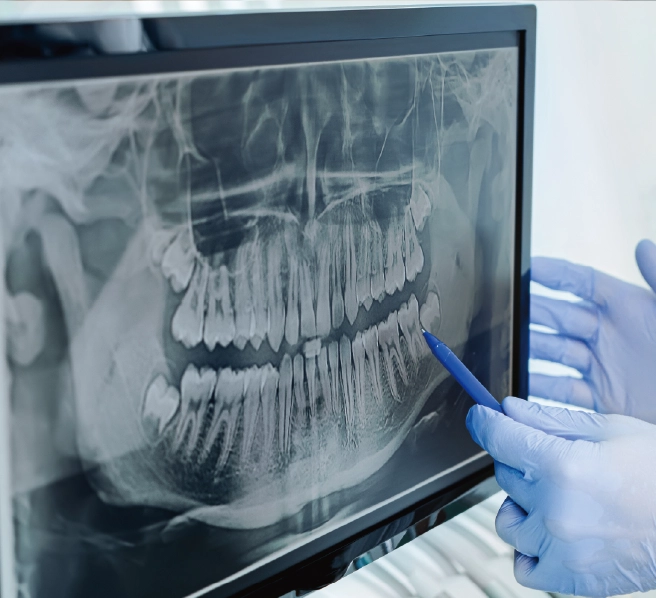

ガミースマイルの診断

当院では、以下のような診査を行い、

ガミースマイルの原因を

一つひとつ丁寧に確認していきます

- ・歯ぐきと歯の境界線から歯をはめ込む穴となる骨の頂点までの長さを測定

- ・歯の表面(エナメル質)となる歯冠部と歯根部境界線の位置を、X線撮影で確認